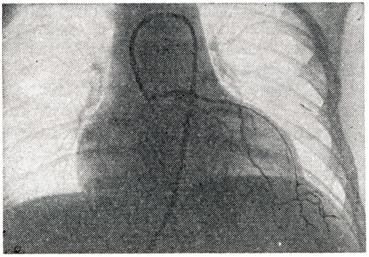

Рис. 5.

Коронарограмма больного через 8 лет после диафрагмопластики диффузной аневризмы сердца. Видна густая сеть анастомозов между сосудами диафрагмы и сердца.